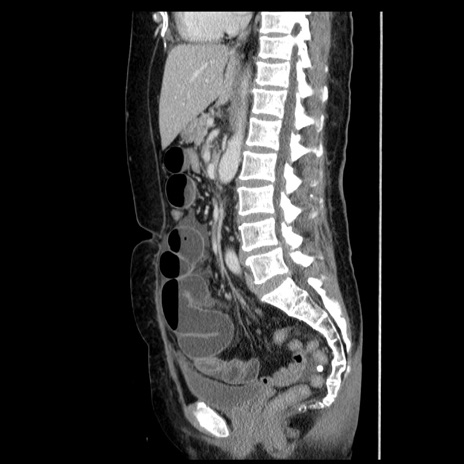

症例6(矢状断像)

【症例】50歳代女性

【主訴】下腹部痛

【現病歴】本日朝より下痢2回あり。 昼食を食べた後、嘔吐3回、下腹部痛認め、症状軽快せず、当院救急搬送。

【既往歴】卵巣癌術後(8年前に当院で卵巣摘出)

【身体所見】 意識清明、腹部:平坦、腸蠕動音→、やや硬、下腹部自発痛・圧痛あり、反跳痛あり、筋性防御なし。

【データ】WBC 16000、CRP 0.01